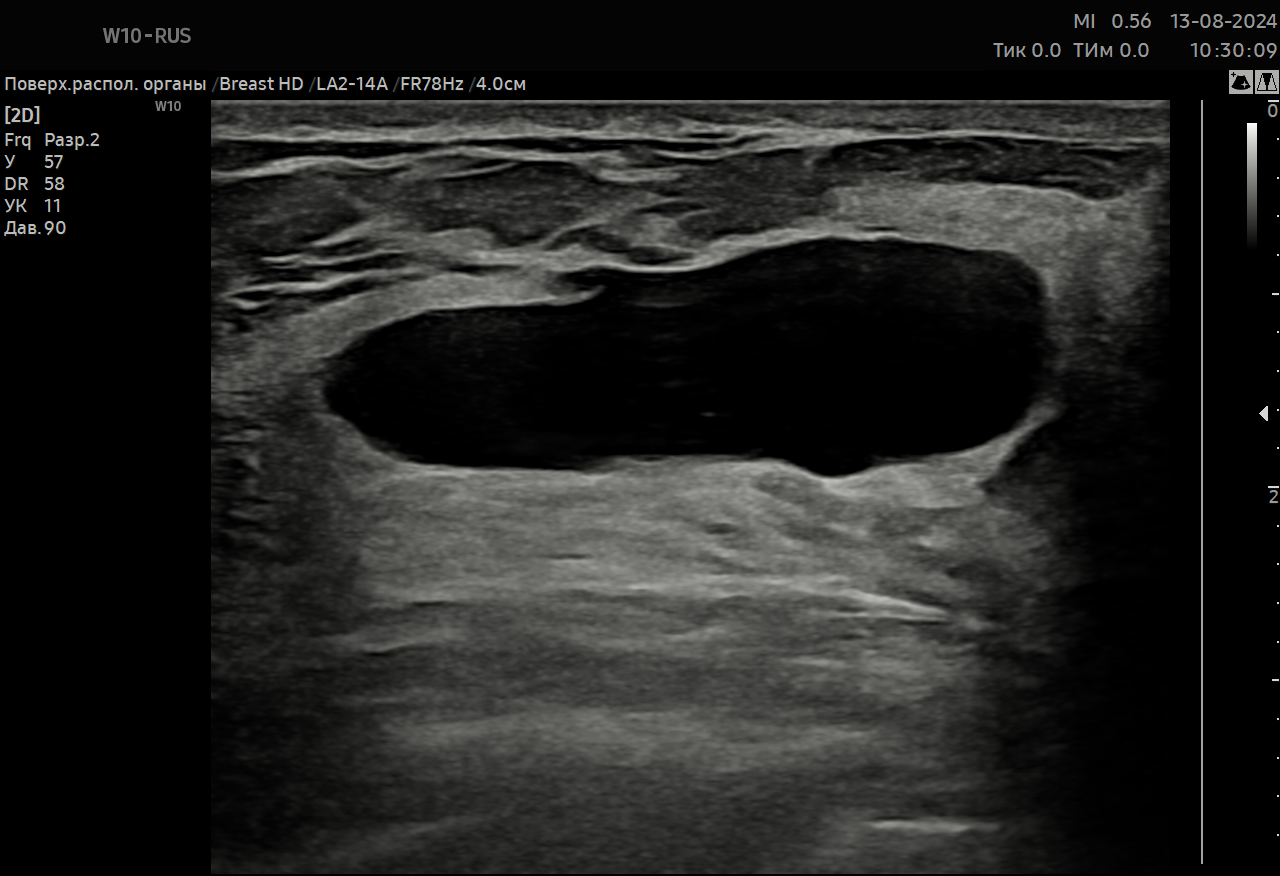

Представлен обзор литературы с демонстрацией собственных клинических наблюдений использования программы автоматического обнаружения и анализа образований молочной железы на основе искусственного интеллекта S-Detect. В целом, по данным литературы, диагностическая точность S-Detect при выявлении злокачественных опухолей молочной железы достигает 86–93%. Ложноположительные результаты S-Detect часто имели место при доброкачественных образованиях больших размеров, а также наличии в них кальцинатов. Ложноотрицательные результаты S-Detect наблюдались при злокачественных опухолях малых размеров, а также отсутствии в них кальцинатов. Вместе с тем ряд авторов подчеркивают повышение диагностической точности при дифференциальной ультразвуковой диагностике маленьких (≤20 мм) образований молочной железы с использованием S-Detect. Имеются данные о том, что при межплоскостной дискордантности S-Detect (противоречащие заключения при оценке в разных плоскостях сканирования) результаты использования S-Detect следует подвергнуть сомнению. В целом диагностическая точность S-Detect сопоставима с результатами использования ультразвуковых контрастов (CEUS) и демонстрирует более высокую точность по сравнению с эластографией. Важное значение имеет использование различных режимов S-Detect (высокая чувствительность, высокая точность, высокая специфичность: в настоящее время представляется оптимальным использовать режим “высокая точность”). В целом S-Detect демонстрирует значительно более высокую специфичность по сравнению с врачом, особенно при оценке образований BI-RADS 4a, однако при этом могут быть пропущены от 1 до 7% злокачественных опухолей. Большинство авторов отмечают, что S-Detect демонстрирует более низкую чувствительность по сравнению с врачом. При этом диагностическая точность S-Detect оказалась выше, чем у доктора с небольшим опытом работы, но она сопоставима с результатами опытного врача. Оказалось, что S-Detect более эффективна при использовании врачами, имеющим небольшой опыт работы (1–2 года), это может значительно снизить количество неоправданных инвазивных вмешательств. При использовании S-Detect врачами-экспертами не отмечалось значимого увеличения точности диагностики. Ряд авторов считают, что S-Detect может быть использована в качестве учебного пособия для начинающих врачей, перспективно использование S-Detect в регионах с ограниченными медицинскими ресурсами, что позволит снизить нагрузку на врачей.

Буланов М.Н. Использование программы автоматического обнаружения и анализа образований на основе искусственного интеллекта S-Detect при ультразвуковом исследовании молочной железы: литературный обзор и собственные клинические наблюдения. Ультразвуковая и функциональная диагностика. 2026;32(1):83-99. https://doi.org/10.24835/1607-0771-371

Bulanov M.N. Use of the artificial intelligence-based S-Detect software for automated detection and analysis for breast ultrasound: a literature review and own clinical cases. Ultrasound & Functional Diagnostics. 2026;32(1):83-99. (In Russ.) https://doi.org/10.24835/1607-0771-371